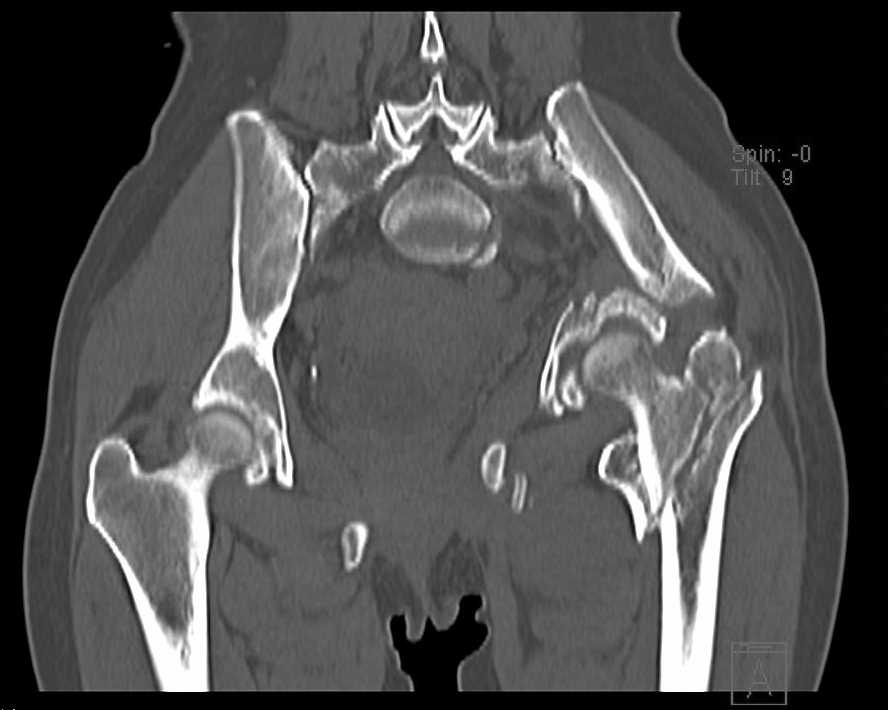

Больная 43 года (промышленный альпинист), 28.07.08 в результате падения с 5 этажа получила политравму: Перелом свода и основания черепа. Вертикально-нестабильное повреждение таза, осложнённое разрывом мочевого пузыря. Чрезвертельный перелом левого бедра. Перелом правой таранной кости, переломовывих правой кубовидной кости. Тупая травма живота, разрыв печени, ушиб почек. Забрюшинная гематома. В день травмы - лапаротомия, ушивание ран печени. Разрыв мочевого пузыря не диагностирован. Течение болезни осложнилось развитием мочевого затёка и обширной пред- и забрюшинной флегмоны, сформировался свищ мочевого пузыря. 19.8.2008 вскрытие, дренировние флегмоны, ревизия мочевого пузыря, обтурация мочевого свища (свищ закрылся в октябре), 1.10.2008 некрэктомия, пластика по Шеде-Лидскому правой кубовидной кости. По результатам КТ диагностирован рак правой почки (диагностическая находка), 8.10.2008 нефрэктомия справа. Переломы велись консервативно. Имеется вертикальное смещение левой половины таза с выраженным отведением крыла (клинически подвижности нет), несросшийся низкий двухколонный перелом левой вертлужной впадины с потерей конгруэнтности, укорочение около5 см, застарелый разрыв лонного сочленения, неправильно сросшиеся переломы обеих ветвей правой лонной кости с укорочением, патологическая подвижность лоно-седалищного фрагмента слева. Правая нижняя конечность неопорна, несмотря на то, что лежа прямую ногу поднимает, ходит на левой ноге (ортопедическая обувь) с костылями, справа тазобедренный ортез. Седалищные нервы работают.Урологи отпустили больную на 6 мес.

Извиняюсь, ошибся : опорная нога у больной правая. Левая нога неопорная, т.к. сращения на уровне бедра и вертлужной впадины нет.